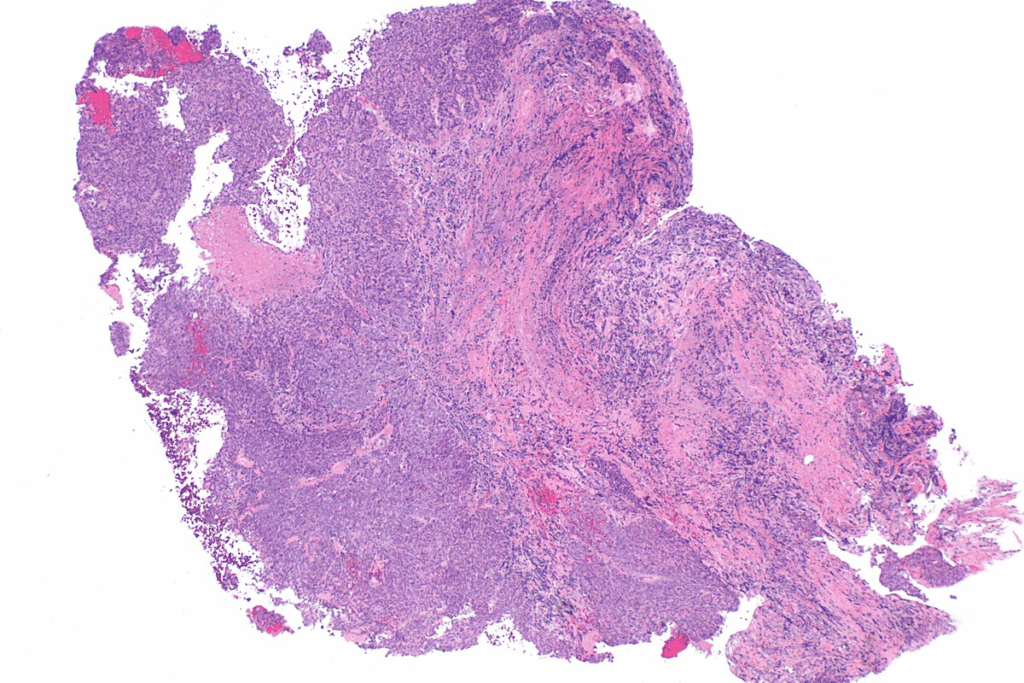

Neuroblastoma starts with neural crest cells. These cells grow into different types of neurons and glial cells in the nervous system.

When neural crest cells don’t mature, they can form tumors called blastomas. Neuroblastoma is a type of blastoma from immature nerve tissue.

The presence of immature cells is key to this disease. Knowing their role helps us find better treatments.

In conclusion, neuroblastoma is linked to neural crest cells and cell differentiation. More research is needed to understand and treat neuroblastoma better. This could help with neuroblastoma staging and improve patient care.